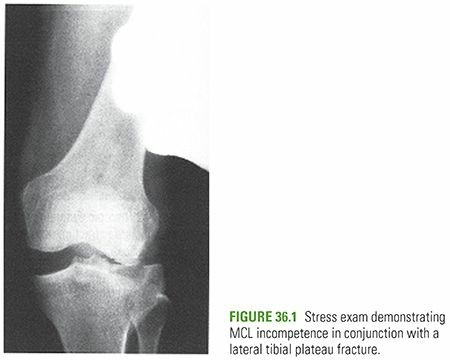

• Joint Instability: Significant instability of the knee joint demonstrated clinically or radiographically, often due to associated ligamentous injury or extensive bony comminution.